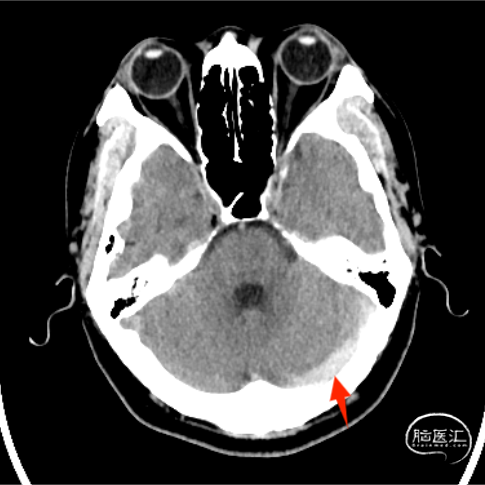

➢2023-12-23 外院头颅CT

现病史:患者1天前无明显诱因下出现反复头痛,头痛位于后枕部,呈持续性胀痛,就诊当日患者头痛加重,至当地查头颅CT提示:双侧横窦、乙状窦高密度影,静脉窦血栓。为进一步诊治,转入我院。

蛛网膜下腔出血

静脉窦血栓